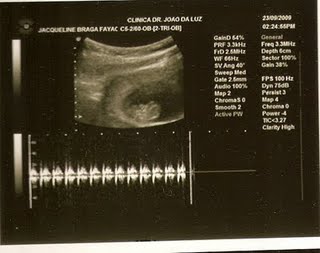

OIE, ontem (17/11) fui fazer a ultra de emergência que a doutora passou, pois não tinha ouvido o coração do meu bebê pelo aparelho...

E lá estava meu bebê se mexendo todo, o coração batendo a 139bpm, com 20 cm e 150g...

Ele colocou a perninha na frente, mas depois tirou e deu até pra ver o sexo: É um meninão...

2º Ultra

Hello, demorei a postar as fotos, mas é que estou sem tempo por causa da facul...O Tcc está me dando uma dor de cabeça...

Meu bb lindinho estava se movimentando todo, ele até chegou a juntar as mãozinhas e dar um tchauzinho, dá pra ver na foto, o coraçãozinho estava batendo forte, deu pra ver a coluna vertebral toda formadinha...

A única coisa que ele não mostrou foi o sexo, o medico nem quis opinar...ele estava na transversal...Que preguicinha que esse Bebê estava...hehehe

Irei fazer outra ultra com 18 semanas, espero que até lá ele já tenha sentado, e que fique com as pernas bem abertas...hohoho

Medidas:

Fêmur: 10mm

Diametro Biparietal: 26mm

Comprimento: 6 cm...